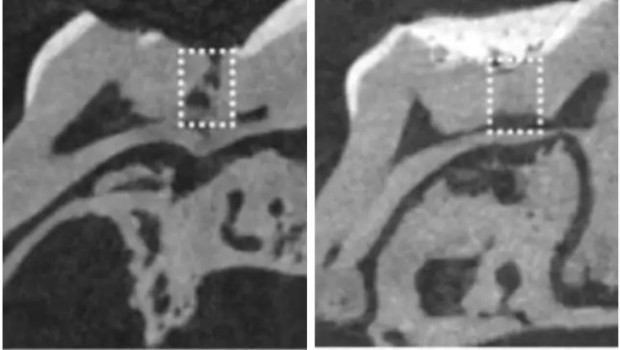

Alzheimer hastalığını tedavi edebilmek için geliştirilmiş olan Tideglusib adındaki yeni bir ilacın fareler üzerinde yapılan denemelerinde, doğal bir diş doldurma mekanizmasını harekete geçirdiği keşfedildi. İlaç, kök hücreleri uyararak, dentin oluşumunu tetikliyor.

Dentin oluşumu diş ömrü boyunca sürdüğünden, yaşlandıkça dentin kalınlığı artıyor. Bu yüzden dentin aynı zamanda insan dişlerine sarı rengini veriyor. Minenin kalınlığı azaldıkça, alttaki dentin tabakası daha fazla görünür hale geliyor. Dişler, aslında herhangi bir dış yardım almadan doğal olarak dentini ancak belli koşullar altında üretebiliyor. Diş özünün (pulpa), enfeksiyona (örneğin çürümeye) veya travmaya maruz kalarak, iç yapının üretimini başlatması gerekiyor. Ancak öyle olduğunda bile, dişin doğal olarak yeniden üretebildiği katman çok ince oluyor; yani genellikle derin olan çürüme kaynaklı oyukları onarmaya yetmiyor.

Bilim Fili sitesi haberine göre , Tideglub ilacı bu durumu değiştiriyor, çünkü “dentin” oluşumuna köstek olan GSK-3 enzimini kapatıyor.